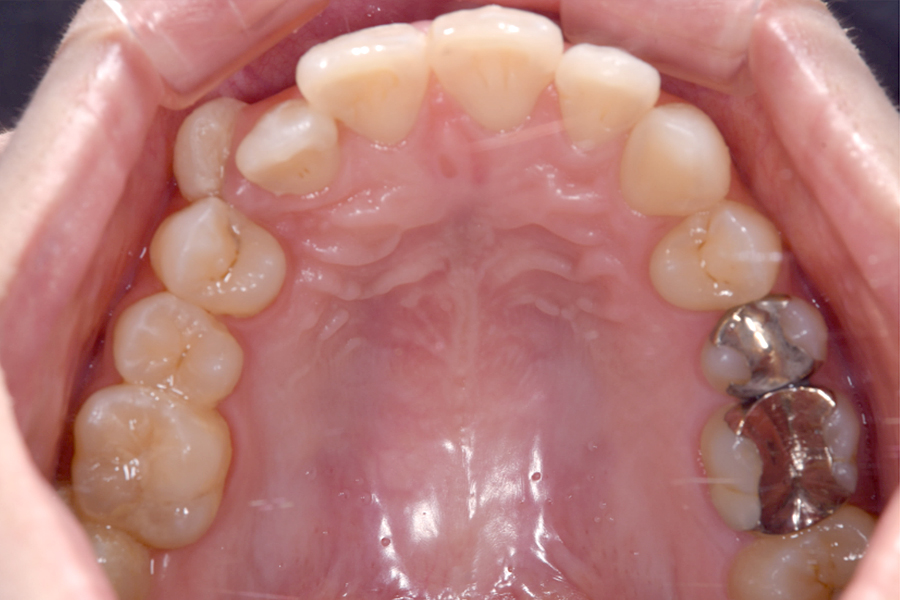

| 主訴 | 見た目を治したい、歯を白くしたい |

|---|---|

| 治療期間 | 1年6か月 |

| 治療費 | マウスピース矯正と ホームホワイトニングセット 1,022,350円(税込) |

| 治療内容 | 目立ちにくいマウスピース矯正 (非抜歯矯正) 歯と歯の間に隙間をつくることにより、歯列弓を広げながら治療を行いました。 また矯正用マウスピースをトレー代わりにし、ジェルを入れてホームホワイトニングを同時に行っております。 |

| 治療のリスク | ・後戻りする可能性があるのでリテーナーを最低でも矯正期間以上はつける必要があります。 ・ホワイトニング後、一時的に痛みが出る場合があります。 |